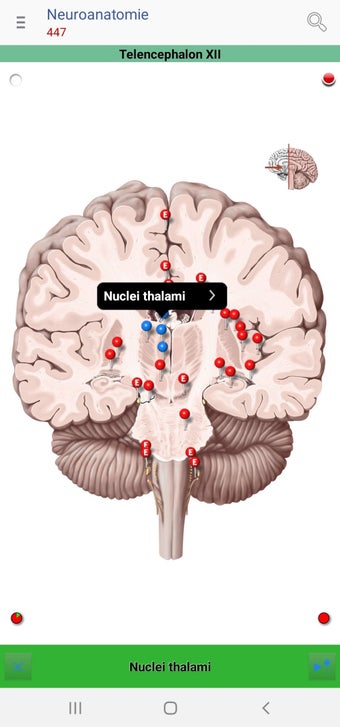

The app consists of different sections, each of which contains information about a specific part of the body. You will learn about the different organs, as well as the muscles, bones, and other important structures. You can test yourself with a unique quiz that consists of multiple-choice questions.